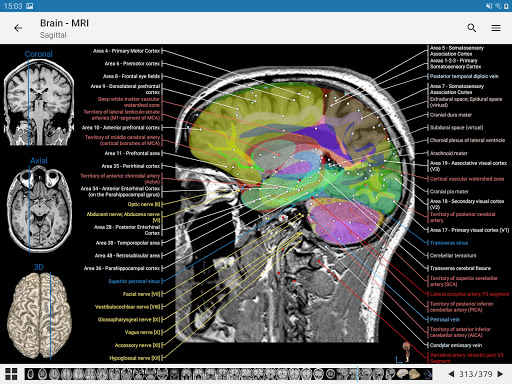

IMAIOS e-Anatomy adalah atlas anatomi manusia untuk dokter, ahli radiologi, mahasiswa kedokteran, dan teknisi radiologi. Dapatkan cuplikan lebih dari 26.000 gambar medis dan anatomi secara gratis sebelum berlangganan atlas anatomi manusia terperinci kami.

e-Anatomy memiliki lebih dari 26.000 gambar yang berisi serangkaian gambar dalam tampilan aksial, koronal, dan sagital serta radiografi, angiografi, gambar diseksi, bagan anatomi, dan ilustrasi. Semua gambar medis diberi label dengan cermat, lebih dari 967.000 label tersedia dalam 12 bahasa termasuk Terminologia Anatomica Latin.

- Gulir set gambar dengan menyeret jari Anda

- Perbesar dan perkecil

- Ketuk label untuk menampilkan struktur anatomi

- Pilih label anatomi berdasarkan kategori

- Mudah menemukan struktur anatomi berkat pencarian indeks